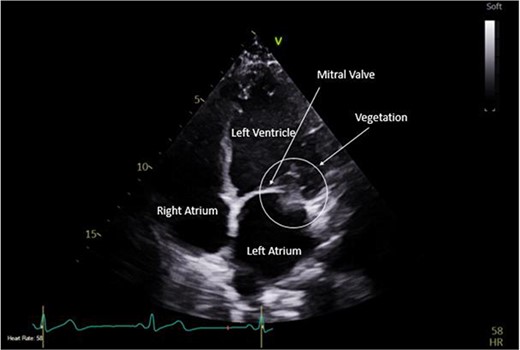

A CTPA was undertaken on Day 2, which excluded pulmonary embolism but confirmed bilateral peri-hilar consolidation and pleural effusions consistent with pneumonia. However, her pulmonary artery was dilated at 32 mm indicative of potential heart failure. On Day 5 of her ICU stay, a transthoracic echocardiogram was undertaken that revealed there to be severe mitral regurgitation including a mobile echogenic mass attached to the underside of the anterior mitral valve leaflet consistent with a vegetation (Figs 1 and 2).

Pre-operative TTE depicting mitral valve with vegetation (labelled).